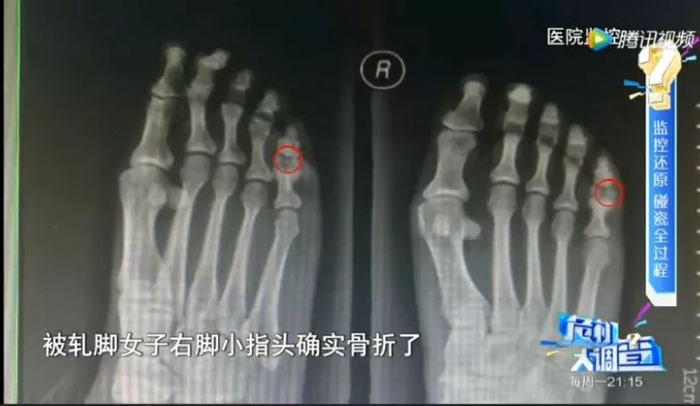

这名碰瓷女子也不是来假的

送往医院后发现脚趾确实骨折了

但事后经调查查明,

她是事前用木槌砸断自己的脚趾!